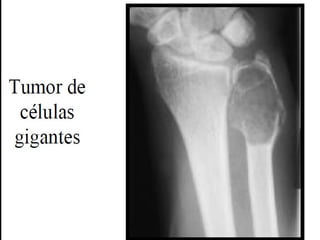

Tumor a células gigantes

Tumor de células gigantes

• Se denomina así por que está constituido por

células multinucleadas gigantes de tipo osteoclasto

(osteoclastoma)

• Es un tumor infrecuente relativamente benigno

pero localmente agresivo.

• Suele aparecer entre la tercera y quinta década.

• Afectan a las epífisis y metáfisis sobre todo en la

rodilla.

• La mayoría son solitarios pero pueden ser múltiples.

Tumor de células

gigantes

- Tumores grandes y de color pardo rojizo que

sufren frecuentemente degeneración quística.

- Están formados por células mononucledas

ovaladas uniformes con membranas celulares

mal definidas, mitosis frecuentes y que parecen

crecer en un sincitio.

- En forma dispersa se observan numerosas

células gigantes de tipo osteoclasto (100 o más

núcleos).

Antonio Ferrández Izquierdo